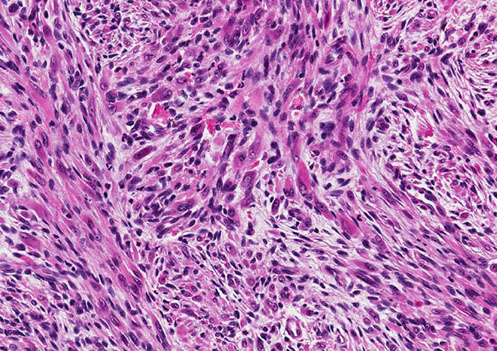

Micro: spindle cells forming slits c extravasated RBCs, hemosiderin laden macrophages, lymphs and fibrosis

- minimal atypia

- can have lots of PAS+ hyaline bodies, which are heme breakdown products

- moderate mits

Stages: Early-patch, later-plaque tumor, and nodular

Nodular - fascicles of spindle cells, separated by slit-like vascular spaces containing erythrocytes, PAS positive diastase resistant hyaline globules, extravasated RBCs, scattered plasma cells, and hemosiderin deposits